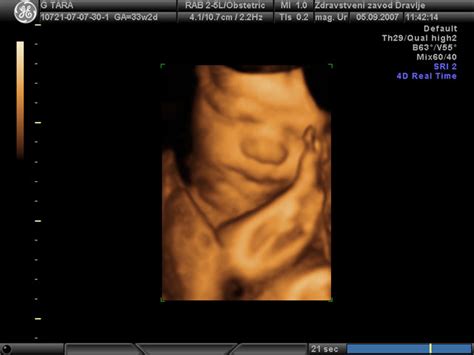

- Ultrazvočni pregledi: Poleg zgodnjega pregleda med 11. in 14. tednom, je ključen tudi morfološki pregled ploda med 19. in 23. tednom, ki omogoča oceno organov in strukture ploda. Dodatni ultrazvočni pregledi se lahko opravijo med 24. in 28. tednom, pa tudi med 35. in 37. tednom, če obstajajo posebne potrebe ali tveganja.

Za obisk te ambulante prejmete napotnico od svojega osebnega ginekologa. Potrebno se je naročiti prek telefona ali elektronske pošte. Na dan pregleda se najprej zglasite v sprejemni ambulanti. V tretjem trimesečju nosečnosti sledi CTG snemanje, kjer se s pomočjo dveh pilot na trebuščku beleži plodov srčni utrip in krčenje maternice. Po vsaj dvajsetih minutah snemanja sledi merjenje krvnega tlaka, telesne teže ter pogovor z babico o osebnih anamnezi, razlogu prihoda in morebitnih vprašanjih. Sledi pregled pri zdravniku, ki po potrebi opravi tudi ultrazvočni pregled.